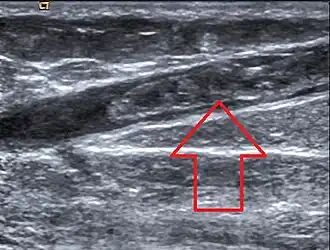

| Trombose da veia safena magna observada no exame de ultrassom | |